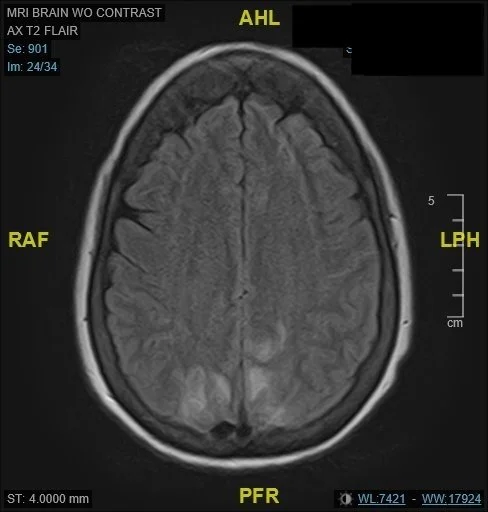

MRI Brain Radiology Impression: “Relatively symmetric T2 lengthening related to the parieto-occipital regions, with possibly a small amount of diffusion restriction, and cortical subarachnoid hemorrhage. The appearance is suggestive of posterior reversible encephalopathy syndrome and/or reversible cerebral vasoconstriction syndrome.”

An MRI was obtained, with findings as above, concerning for posterior reversible encephalopathy syndrome and/or reversible cerebral vasoconstriction syndrome.